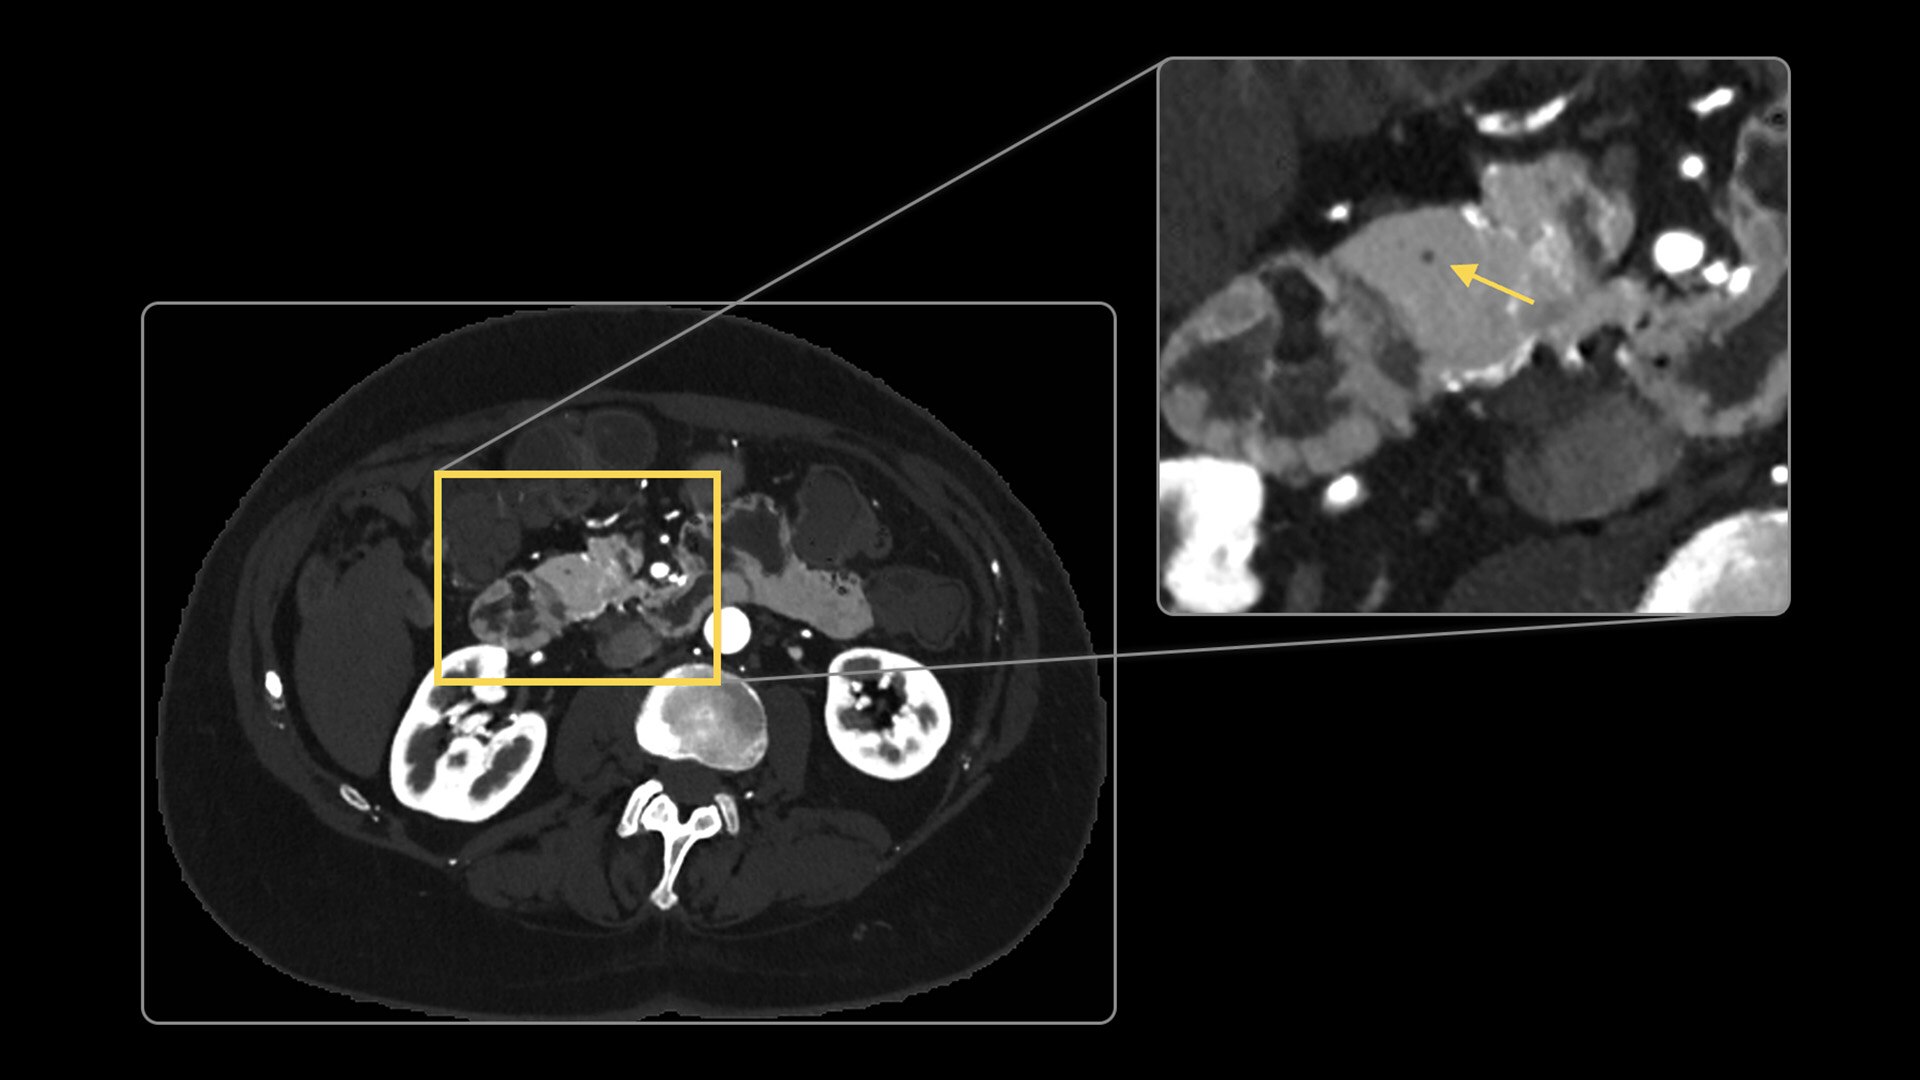

Our advanced spectral imaging capabilities are intended to allow you to experience the difference between seeing and knowing so you can confidently detect, characterize and monitor disease.

Photonova Spectra is also designed to enhance material separation for tissue characterization and disease quantification, bringing potentially greater diagnostic confidence in every acquisition across care areas.

A full range of spectral imaging series is generated natively on console and available for transfer to PACS. The full-fidelity spectral data acquisition is intended to provide native DICOM images and material maps to support clinical diagnosis, with improvements of up to 4x enhanced energy discretization1, 2x higher material map spatial resolution2, and 2x improved iodine detectability3.